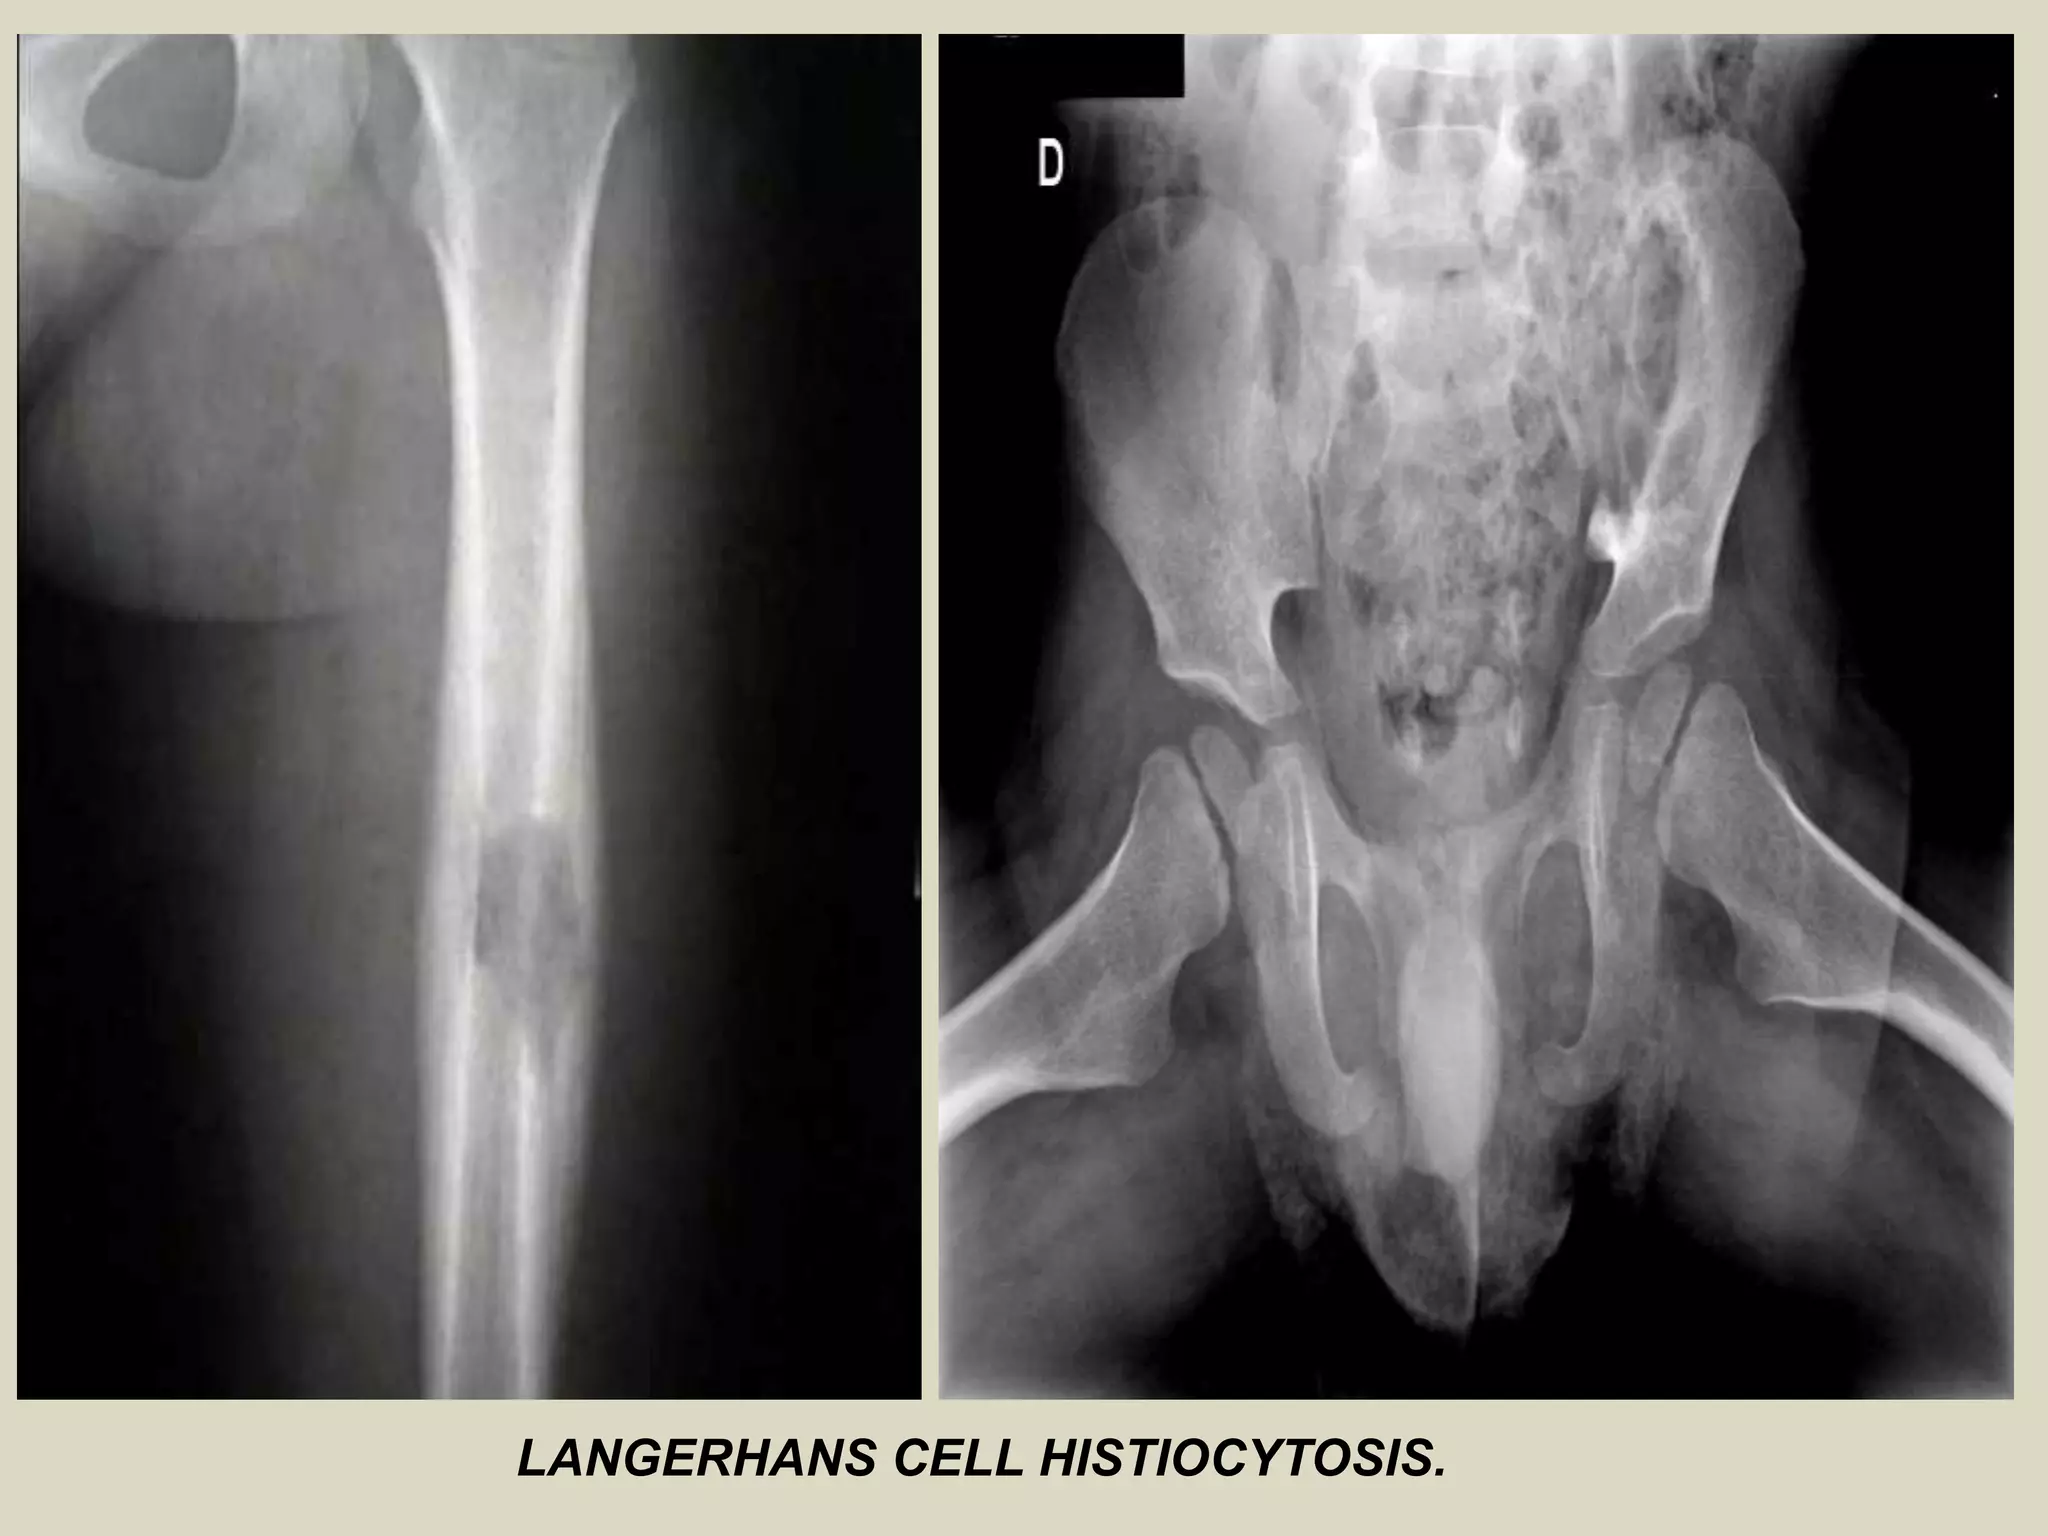

LANGERHANS CELL HISTIOCYTOSIS (EOSINOPHILIC GRANULOMA) OF BONE

- Previously known as histiocytosis X, is an intraosseous mass of proliferating

Langerhans cells.

- Langerhans cells are dendritic cells that normally populate the skin, mucosal

surfaces, lymph nodes and other tissues where they function as specialized

antigen presenting cells.

- In Langerhans cell histiocytosis, the proliferating cells are monoclonal,

supporting the theory that the disease is neoplastic.

Epidemiology:

- LCH is relatively rare disorder, accounting for less than 1% of all osseous l

lesions.

- Age distribution is ranging from the first month to 8th decade of life with

80-85% of cases seen in patients under the age of 30, and 60% under the age

of 10.

- Males are affected twice as often as females.

Sites of involvement:

- Any bone may be involved, although there is predilection for LCH to involve

the bones of the skull, notably the calvarium.

- Other frequently involved sites include the femur, the bones of the pelvis,

and the mandible.

Imaging:

- LCH lesions are well defined and lytic on radiographs, however, in a minority

of cases may have ill-defined and permeative margins.

- Cortical involvement may elicit a periosteal reaction.

- Complete resolution of radiographic abnormalities may follow

treatment or occasionally occurs spontaneously.

LANGERHANS CELL HISTIOCYTOSIS.

LANGERHANS CELL HISTIOCYTOSIS .